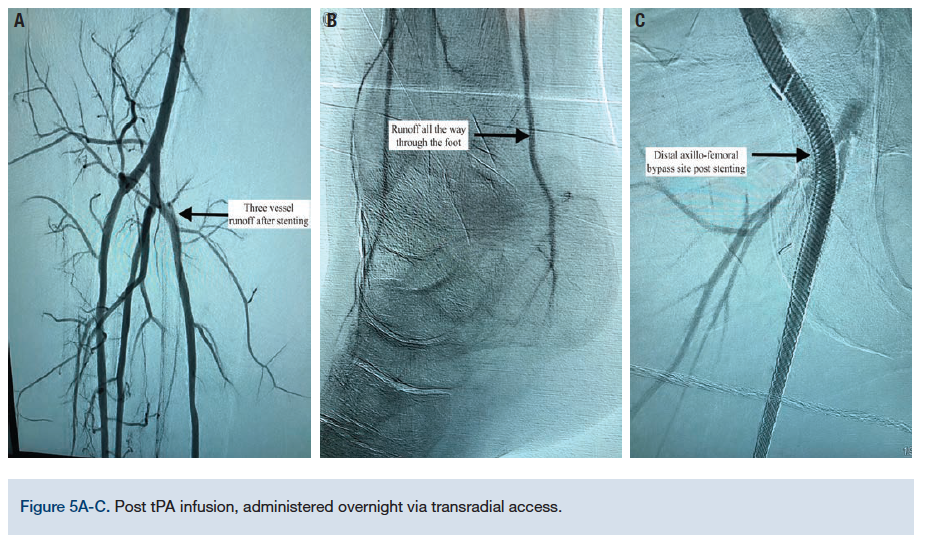

The right dorsalis pedis artery was accessed using ultrasound guidance and a 6 French (Fr) system was used. An .035-inch Quick-Cross catheter (Philips) was advanced from the transpedal access into the superficial femoral artery (SFA) for selective angiography, revealing the subtotal occlusion at the level of the femoral and popliteal arteries (Figure 1). The .035-inch wire and catheter were able to advance through the occlusion and into the axillary bypass graft. However, no equipment had the appropriate length to extend further into the axilla. The decision was made to proceed with transradial access to allow for both antegrade and retrograde approaches to revascularization. An .035-inch guidewire was positioned in the axillary bypass as a marker for locating the graft from the arm.

The radial artery was accessed using palpation and another 6 Fr sheath was placed. Selective angiography of the subclavian was obtained, which showed flush occlusion of the axillary bypass graft (Figure 2). A left internal mammary artery (LIMA) catheter was used via the transradial approach and an .014-inch wire was successful in crossing the ostial occlusion of the graft with the pedal guidewire as a marker. Through transradial access, 6.0 mm balloon angioplasty was performed successfully of the entire length of the bypass graft and a Supera self-expanding stent (Abbott Vascular) was deployed with excellent results (Figures 3-4). For more precise deployment, a self-expanding Innova stent (Boston Scientific) was deployed in the ostial part of the graft (Figures 3-4). The right SFA was treated via transpedal access with a combination of atherectomy, mechanical thrombectomy, and stenting. Finally, a tPA infusion was administered overnight through the transradial access (with the tip of the infusion catheter placed in the proximal axillary graft) (angiographic results, Figures 5A-C). To complete this complex procedure, <1 gray (Gy) of radiation was required, significantly less than a level that would cause concern for acute radiation side effects.